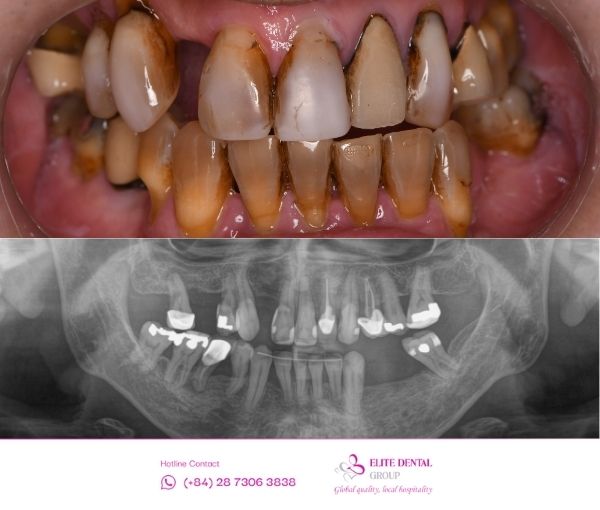

Sau khi thăm khám lâm sàng kỹ lưỡng, đặc biệt là phân tích hình ảnh chuyên sâu bằng máy 3D Conebeam CT, Bác sĩ Lâm xác định tình trạng của anh Tuyến đã trở nên phức tạp hơn do thời gian dài chưa được điều trị khắc phục:

- Viêm nha chu kéo dài: Ảnh hưởng đến sức khỏe tổng thể của nướu và mô nâng đỡ răng.

- Tiêu xương nghiêm trọng: Mật độ và thể tích xương hàm đã bị tiêu giảm ở các vị trí mất răng, đòi hỏi phải can thiệp xử lý nền xương để đảm bảo trụ Implant có thể ổn định.